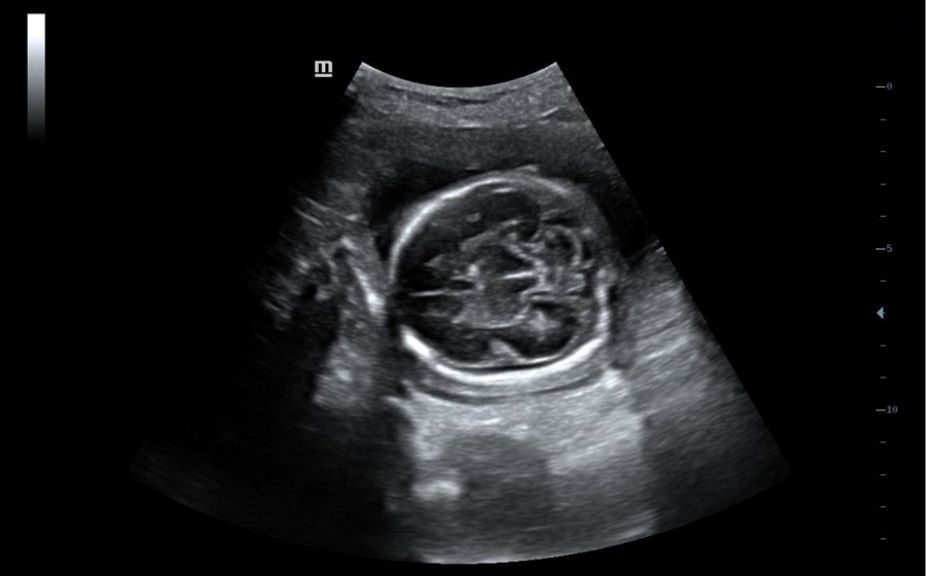

Анатомические иллюстрации, включающие схемы и УЗИ-изображения.

Боковое отображение стандартной эхограммы, обеспечивающее визуальное наведение на изучаемую область.

Стандартные эхоизображения

Сравнение результатов сканирования в реальном времени для справки.